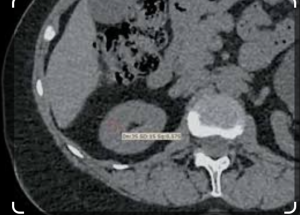

Определение рационального метода расчета средних значений плотности паренхимы почек. Для определения рационального и точного метода расчета средних значений плотности паренхимы почек было проведено сравнение двух подходов:

— измерение денситометрических показателей паренхимы на трех аксиальных срезах (в области полюсов и в середине почечной паренхимы) круглым ROI и получение среднего арифметического этих измерений (рис. 4) — первый метод;

— измерение денситометрических показателей во фронтальном срезе с помощью инструмента для произвольного обведения контуров почки (рис. 5) — второй метод.

Также на основе промежуточной выборки исследований (120 пациентов) определен оптимальный метод оценки средних значений денситометрических показателей паренхимы почек. Для этого осуществлен корреляционный анализ результатов обоих изучаемых методов (первый метод — измерение круглым ROI, второй метод — измерение во фронтальном срезе) в сопоставлении с методом автоматической сегментации почек (рис. 9, а, б).

Полученное значение коэффициента корреляции для первого метода — по отдельным измерениям, составило 0,988 (p<0,001); коэффициента ковариации — 0,76 (p<0,001). Для второго метода — при обведении площади — значение коэффициента корреляции составило 0,987 (p<0,001); коэффициента ковариации — 0,73 (p<0,001). Представленные результаты свидетельствуют о высокой положительной связи.

Корреляционный анализ данных методов продемонстрировал, что обе методики допустимо использовать для измерения денситометрических значений паренхимы почек. Однако менее трудозатратная методика оценки по трем измерениям круглым ROI (первый метод) оказалась не менее точной, чем методика по одному измерению во фронтальном срезе (второй метод) при несколько лучших показателях ковариации, что позволяет остановить выбор для дальнейших расчетов на первом методе.

При сравнении двух методов оценки средней плотности (с помощью измерения круглыми ROI на аксиальных срезах и одно ROI при обведении контура на фронтальном срезе) было отмечено, что оба подхода показали высокую корреляцию (0,988 и 0,987 соответственно) с результатами автоматической сегментации. Небольшое преимущество метода трех ROI в аксиальной плоскости (ковариация 0,76 против 0,73) делает его предпочтительным, хотя оба метода приемлемы. Выбор был остановлен на методе, основанном на измерении в трех ROI, так как он более удобен в практической работе.